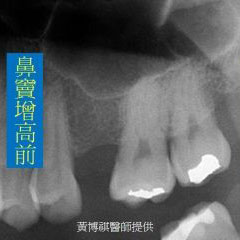

一般而言,口腔內的上顎後牙區,和鼻竇腔只有一層薄薄的上顎骨相隔。因此,上顎後牙區在做 植牙手術之前,都需要先進行鼻竇增高術,來增加上顎骨厚度。 |

微創型鼻竇增高術是利用"鼻竇挺"輕輕將人工骨粉推入鼻竇腔。由連續X光片可以看到,人工骨 粉慢慢地被送進鼻竇腔中。 |